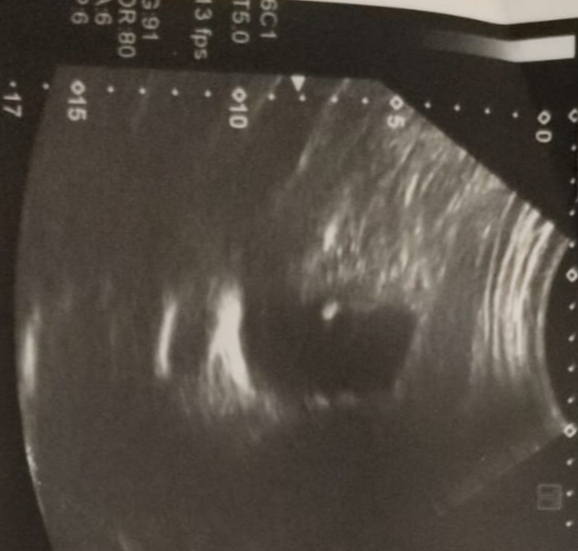

L Lawliet, К Абдурахманову едем на консультации с последующей госпитализацией. Я очень надеюсь на это. К сожалению, все что в моих силах я делаю, но до поездки в Москву наша задача снизить билирубин, который растет и компенсировать печень. Только, что мужу сделали гастроэндоскопию, результаты мне ещё не известны. Жду, когда муж выйдет на связь. Позже выложу заключение.

Раз едете к Абдурахманову Д.Т., то вы уже на правильном пути, грамотный врач. Много видел видео с его участием в конференциях касаемых проблем с печенью. Обязательно нужно делать МРТ с Примовистом с целью диагностики онкологи и расшифровывать у грамотного рентгенолога. При таких показателях высокий риск ее развития, так же анализы говорят за плохое состояние печени. Варианты решения вопросов есть. Думаю врач разложит все по полочкам. Альбумин падает, может способствовать развитию асцита, сразу уточните у Джамала Тиновича, можно ли будет у них прокапать альбумин при необходимости, чтоб потом не бегать в поисках где его взять. Когда планируется консультация? Время в таких ситуациях лучше не тянуть. Я бы сразу перед консультацией сделал ОАК, БАК, коагулограмму, АФП, РЭА, СП19-9 и МРТ или КТ с контрастом (описание и диски), плюс будет ФГДС это тоже хорошо. Удачи в лечении.